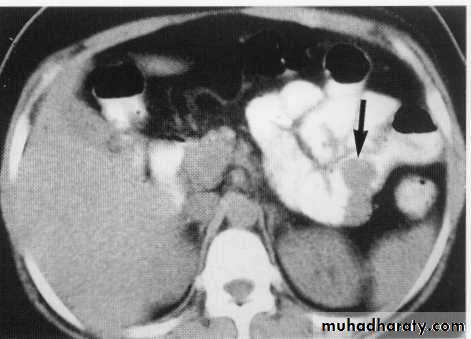

Ct scan carinal LAP